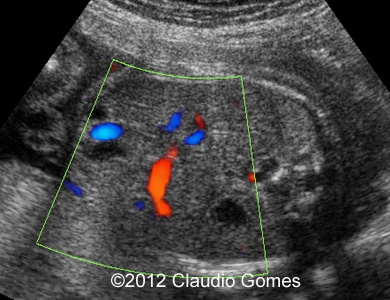

Images 8-11: Persistent right umbilical vein and Inferior vena cava interruption with continuity of the flow via Azygos vein on grayscale and color Doppler

Fig8

Fig9

Fig10

Fig11